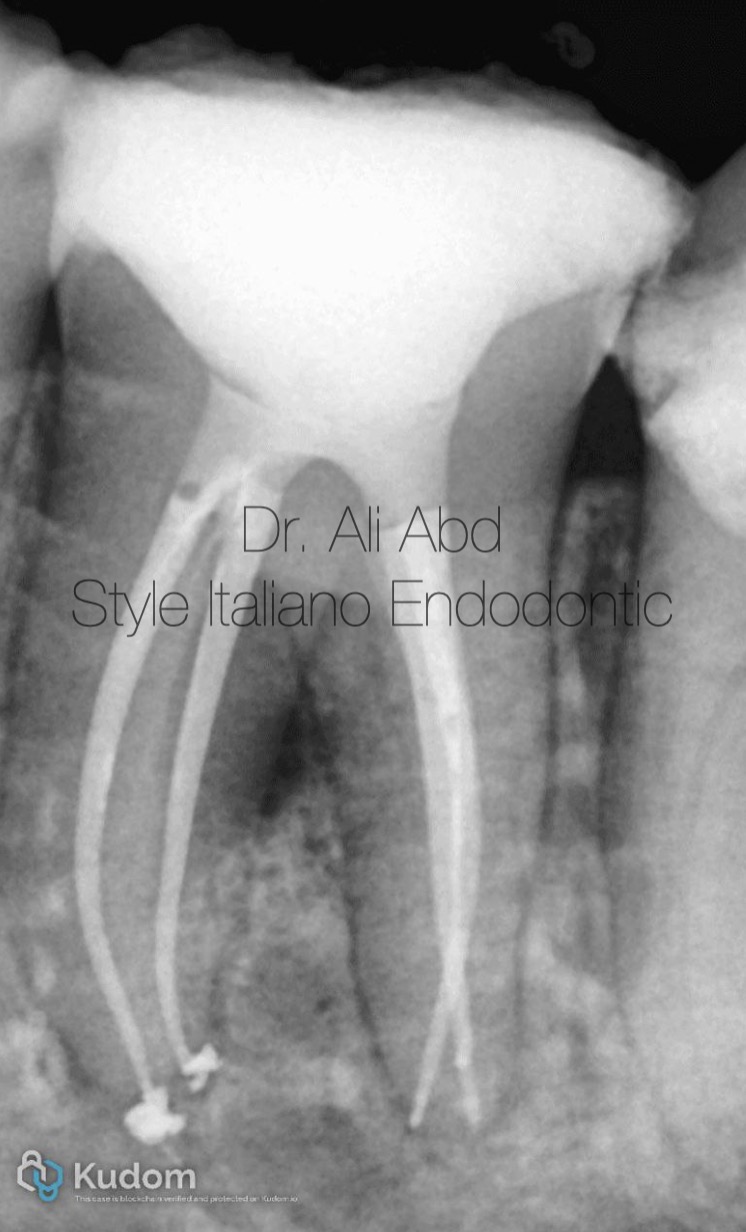

A tooth number #37 with previously initiated therapy due to Acute irrivesible pulptis

From the preoberative x-ray The tooth has a multiplaner curvature ..

So its cosidered a "difficult case" ( sever or modurate curvature , partialy calcified , very tiny canal )

Fig. 6

The files sequence protocol for shaping such cases is :

15/3 up to middle third (coronal glide path)

25/6 up to middle third (coronal preflaring )

15/3 for FWL In OTR or OGP mode (glide path preparation )

20/4 , 25/4 for FWL